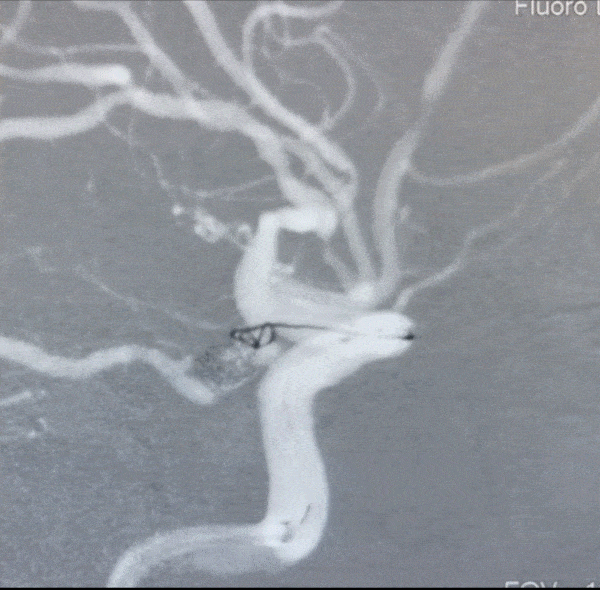

术后蒙片可见支架、子瘤内的弹簧圈、母瘤内的弹簧圈,以及支撑在后交通动脉壶腹内的弹簧圈的两个环

术后右颈内动脉工作位造影,显示动脉瘤完全闭塞,后交通动脉畅通无阻,perfect!